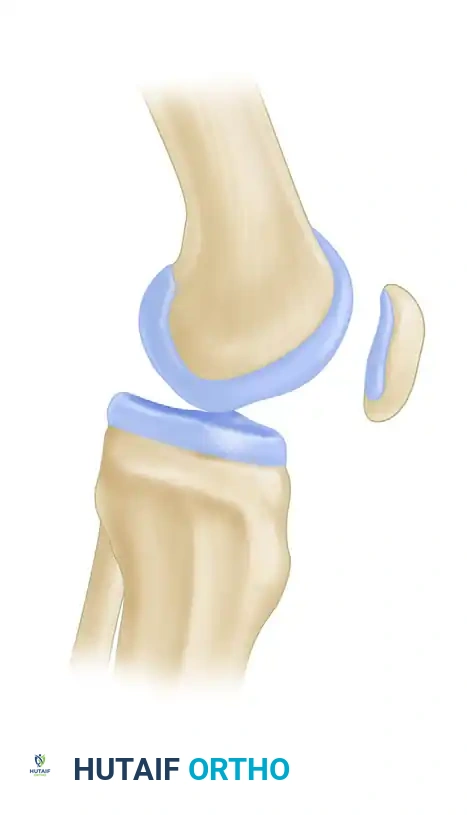

The patellofemoral joint is a complex articulation governed by an intricate balance of static and dynamic stabilizers. The patella functions primarily as a biomechanical fulcrum, increasing the moment arm of the quadriceps mechanism and enhancing extension torque. Pathologies of the patellofemoral joint—ranging from anterior knee pain syndromes to recurrent patellar instability and advanced arthropathy—require a meticulous, evidence-based approach to radiographic evaluation.

The lateral view of the knee is arguably the most informative plain radiograph for assessing patellar height and trochlear dysplasia. A true lateral radiograph—defined by the perfect superimposition of the posterior femoral condyles—is mandatory.

Patella alta (a high-riding patella) is a primary risk factor for patellofemoral instability, as it delays the engagement of the patella into the stabilizing bony confines of the trochlear groove during early flexion.

The axial view is the most important routine projection for assessing the dynamic relationship of the patellofemoral joint. Several techniques exist (Merchant, Laurin, Sunrise), but standardization is key.

When evaluating the axial view, the surgeon must assess the congruence angle, lateral patellofemoral angle, and patellar tilt. Normally, the patella is evenly seated within the trochlear sulcus, with symmetric joint space between the medial and lateral facets and the corresponding femoral surfaces.

Abnormalities manifest as lateral patellar tilt, lateral subluxation, or complete dislocation. Progressive lateral tilt causes the median ridge of the patella to superimpose on the lateral facet, ultimately displacing posterior to it in severe cases.